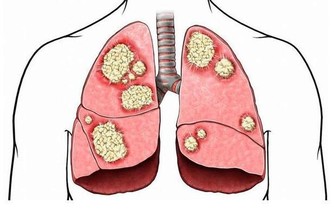

有時候指甲的形狀會出現2種改變方式,一種是指甲呈現扁圓狀改變,另一種則呈現半圓形改變。如果你的指甲扁圓形改變,說明你的腸味淤積的毒素過多,可能還伴有慢性腸炎、消化不良等腸胃疾病。一般此類病人還會有營養代謝障礙,這樣一來就會影響其他臟器的正常運行,特別是對肺部的影響較大。